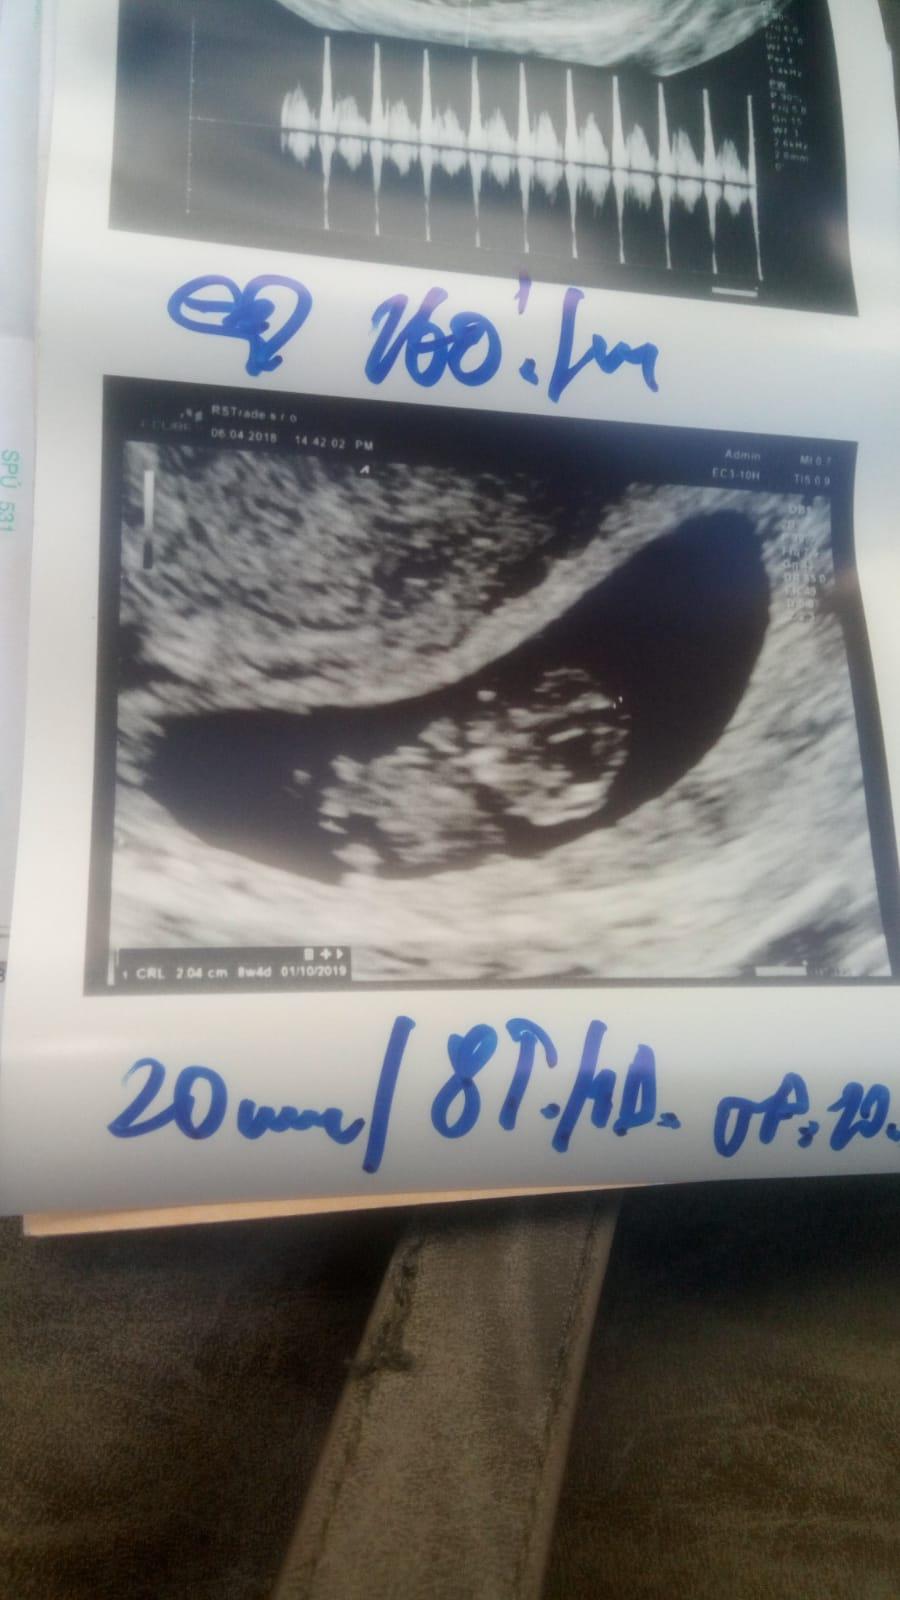

Moje prve dopadlo missed.. A teraz som v 9podla mojich vypoctou a poslednej ms.. Ale podla doktora asi podla velkosti plodu v 8..😊

A pocula som srdiecko je to krasny pocit a bola som pred 2dnami na kontrole a mali sme hlaavku, nozicky ruzicky 😊😊😊😊maly chrustik

@tinka0000 to mi je luto 😞.. Ach nechapem takyto pristup ved to je taka citliva zalezitost... Ja som si merala teplotu takze cca asi viem kedy bola ovulka aj priznaky mam bolesti v podbrusku unava zle mi je ked som hladna aj ked sa najem... Aj testy mam hned uplne silne kolajnice ale tak v 6tt+4 mi prislo ze to bolo este malicke kukni na fotku..

Po 5 tyzdni sa meria velkost gestacneho vaku/GSD/, od siesteho zltkoveho vaku/YS/ a neskor sa meria CRL velkost embrya od hlavicky po kostrc.. DO 12 tyzdna je najpresnejsie urcit podla CRL velkost plodu a to hlavne u zien, ktore maju nepravidelny cyklus a nevedia kedy cca ovulovali...To je najpresnejsie meranie a podla toho by sa malo riadit az do konca tehotenstva datum porodu..V druhom a tretom trimestri sa robia merania ako BPD, FL, HC,AC, ale uz sa nema upravovat termin porodu, pretoze v tychto tyzdnoch kazde dietatko rastie inak a su to len orientacne udaje na vypocet vahy babatka...Termin porodu ma byt vzdy stanoveny v prvom trimestri!